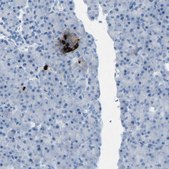

Anti-SST antibody produced in rabbit, a Prestige Antibody, is developed and validated by the Human Protein Atlas (HPA) project . Each antibody is tested by immunohistochemistry against hundreds of normal and disease tissues. These images can be viewed on the Human Protein Atlas (HPA) site by clicking on the Image Gallery link. The antibodies are also tested using immunofluorescence and western blotting. To view these protocols and other useful information about Prestige Antibodies and the HPA, visit sigma.com/prestige.

These images and the collection of this vast data set can be viewed on the Human Protein Atlas (HPA) site by clicking on the Image Gallery link. We also provide Prestige Antibodies® protocols and other useful information.

• IHC tissue array of 44 normal human tissues and 20 of the most common cancer type tissues.